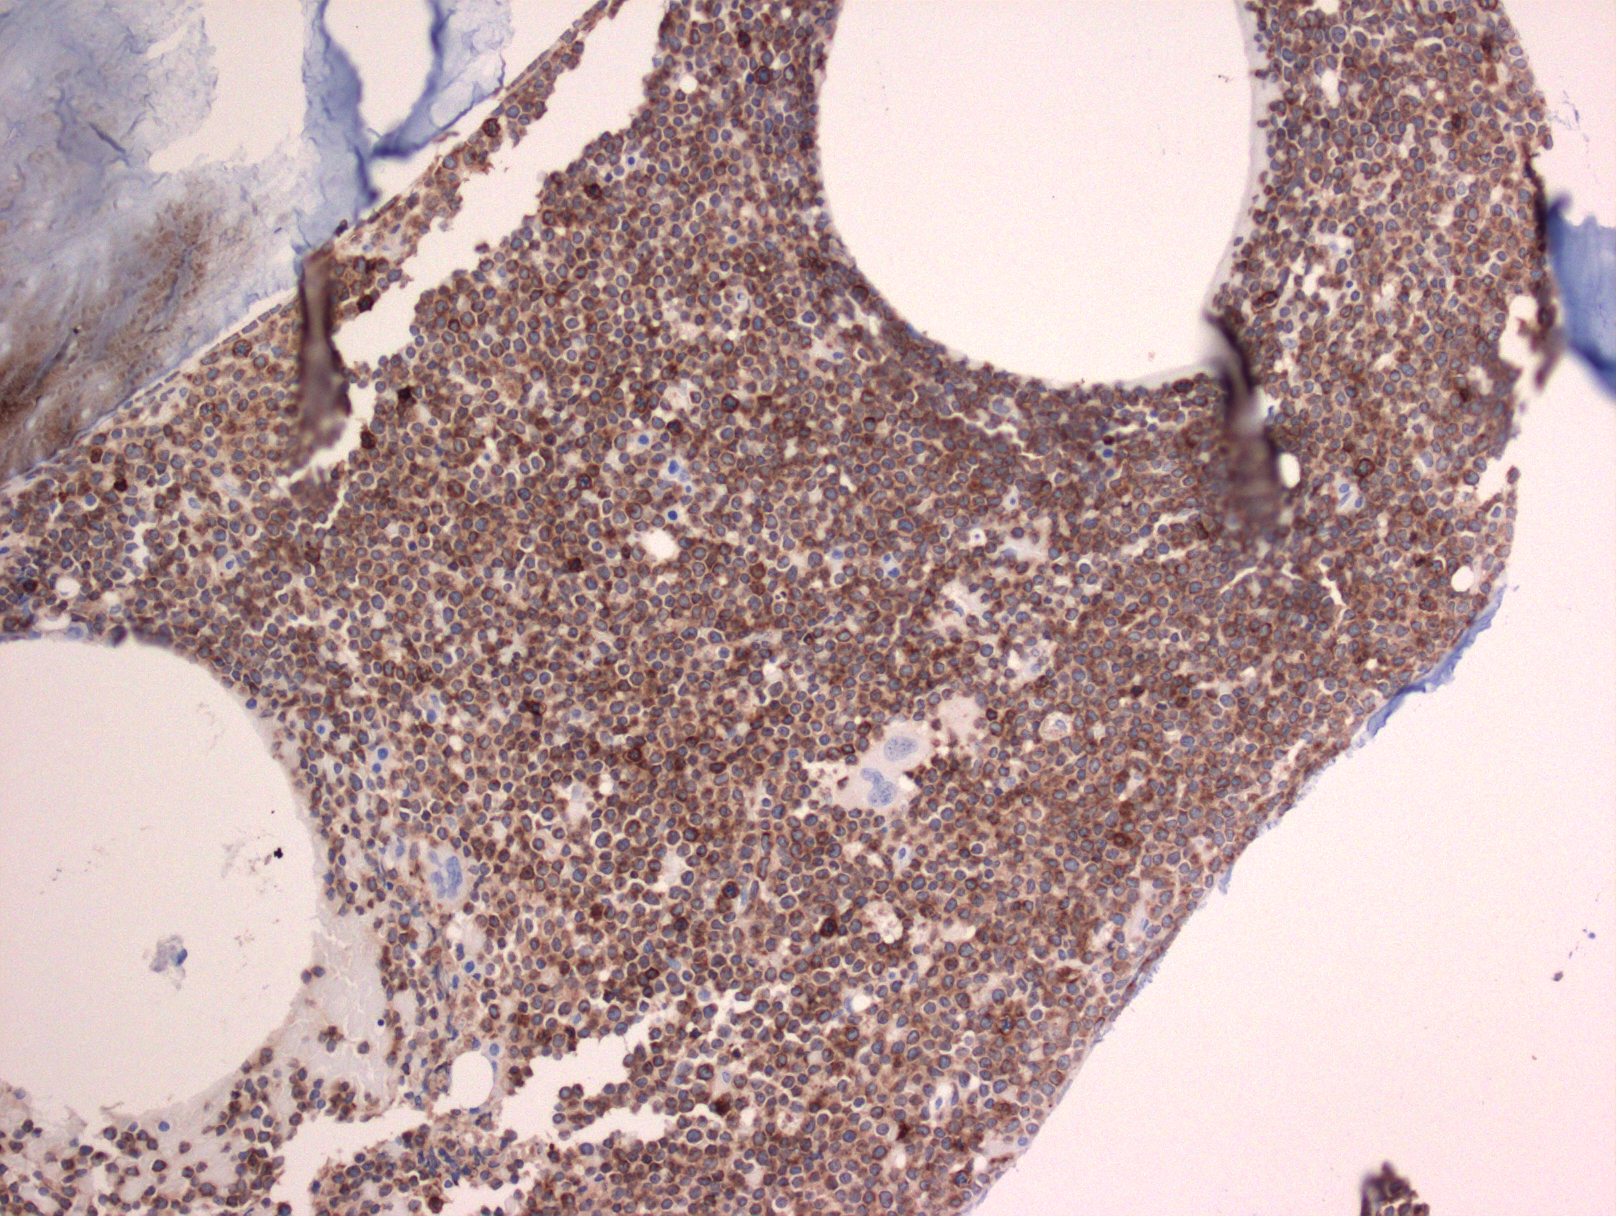

- 髓外受累的部位病变通常呈弥漫性分布,偶尔也可出现部分淋巴结受累,核分裂像多,可见灶性“星空”现象。

- 免疫表型: T-ALL/LBL 中淋巴母细胞呈 TdT 阳性,可表达 CD1a、CD2. CD3. CD4. CD5. CD7 和 CD8 中的一种或多种,最常见的是 CD7 和胞浆 CD3ε 阳性表达,其中只有 CD3 具有确定肿瘤细胞来源的特异性。CD4 和 CD8 常有合表达,CD10 也可以阳性;但这些都不具特异性。不成熟抗原除 TdT、CD1a、CD34 外,CD99 的表达也可表明其前体细胞的特性。部分病例表达 TAL1(核染)。偶有病例 CD117 阳性(常伴有 FLT3 突变)。10%病例表达 CD79a,少数可以表达 CD13 和/或 CD33。根据分化阶段不同,可将 T-ALL 分为以下几型:原 T(Pro-T):cCD3+、CD7+、CD2-、CD1a-、CD34-/+、CD4-、CD8-;前 T (Pre-T):cCD3+、CD7+、CD2+、CD1a-、CD34+/-、CD4-、CD8-;皮质 T(cortical T):cCD3+、CD7+、CD2+、CD1a +、CD34-、CD4+、CD8+;髓质 T(medullary T):cCD3+、CD7+、CD2+、CD1a-、CD34-、sCD3+、CD4 或 CD8 阳性。前两型中的很多病例符合 WHO 2017 年版分类中的早期前 T 淋巴母细胞白血病 (见下)。